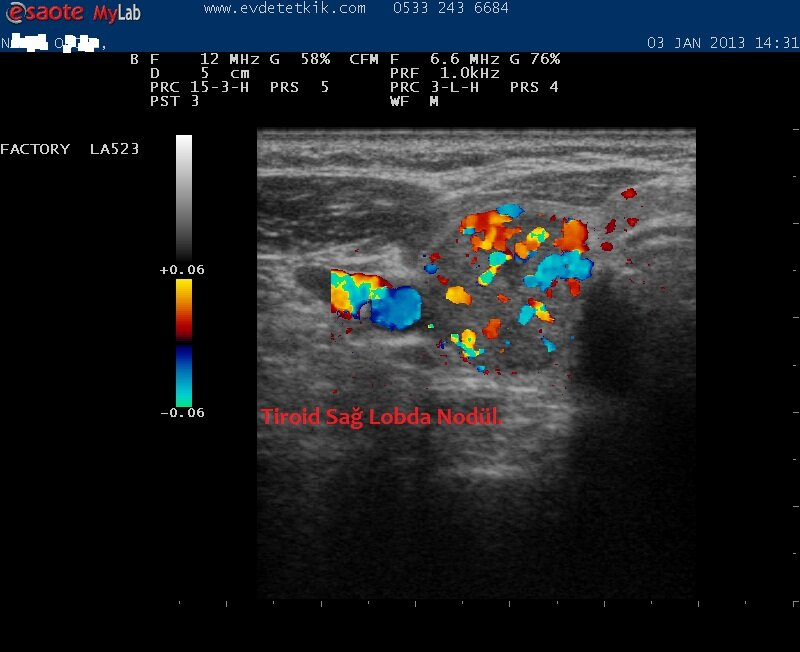

Hizmetimizden görüntüler